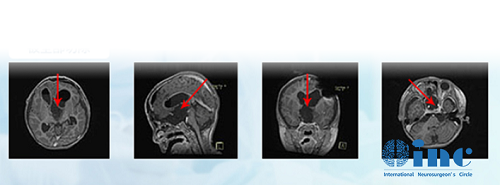

德国巴教授INI手术结果